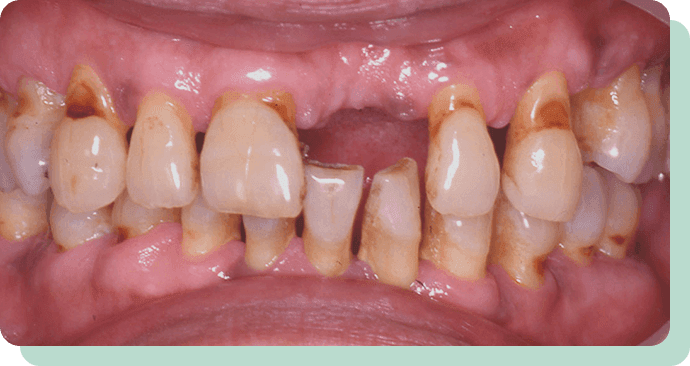

処置前後

左の写真は、歯周病が進んで、どんどん歯が抜けていっている状態です。

この方は、歯を短くし、金属のキャップの上に特殊な入れ歯を装着。

これにより、快適にお食事ができるようになりました。